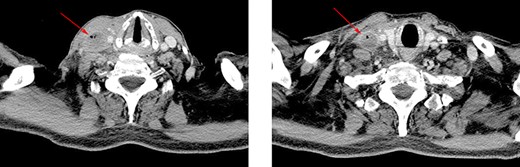

Axial CT view. Image shows a large diameter of right internal jugular vein and air bubbles inside the vessel.

Forty-eight hours later, the patient presented self-limited abdominal bleeding probably related to high dose of low molecular weight heparin (LMWH), which was treated conservatively. At the same time, hiccups appeared. It initially responded positively to haloperidol and chlorpromazine, but it progressed in frequency and intensity, becoming uncontrollable. A CT scan confirmed the absence of intraabdominal complication, and the patient was admitted to the intensive unit care to intensify hiccup treatment. During the next days, he started with fever peaks. Bacteraemia related to CVC was diagnosed, as well as inflammatory signs on the right jugular venous access. Due to the previous findings, a cervicothoracic CT was performed showing a thrombus and air bubbles into the right jugular vein. This conditioned a dilatation of an area of the vein intimately related to the phrenic nerve.

Different agents have been associated to hiccups etiology, which stimulate central or peripheral structures of the hiccups’ reflex arc [1, 2, 4]. Some of these agents, such as trauma, tumors, infections or metabolic diseases, produce persistent hiccups (lasting more of 48 hours) or even untreatable (2 or more months lasting) [1, 4]. In this patient, hiccup etiology was difficult to identify and resulted in a diagnostic challenge, because fever and cervical inflammatory signs appeared days after hiccups. When signs and symptoms came together, a cervical TC was performed, concluding that manipulation of CVC led to a septic thrombosis of internal jugular vein, its dilatation and, finally, the direct compressive stimulation of phrenic and vagus nerves (Figs. 1 and 2). Topaz et al described a case of uncontrollable hiccups after the insertion of a catheter into jugular internal vein because of the compression of phrenic nerve due to a hematoma [2, 3].